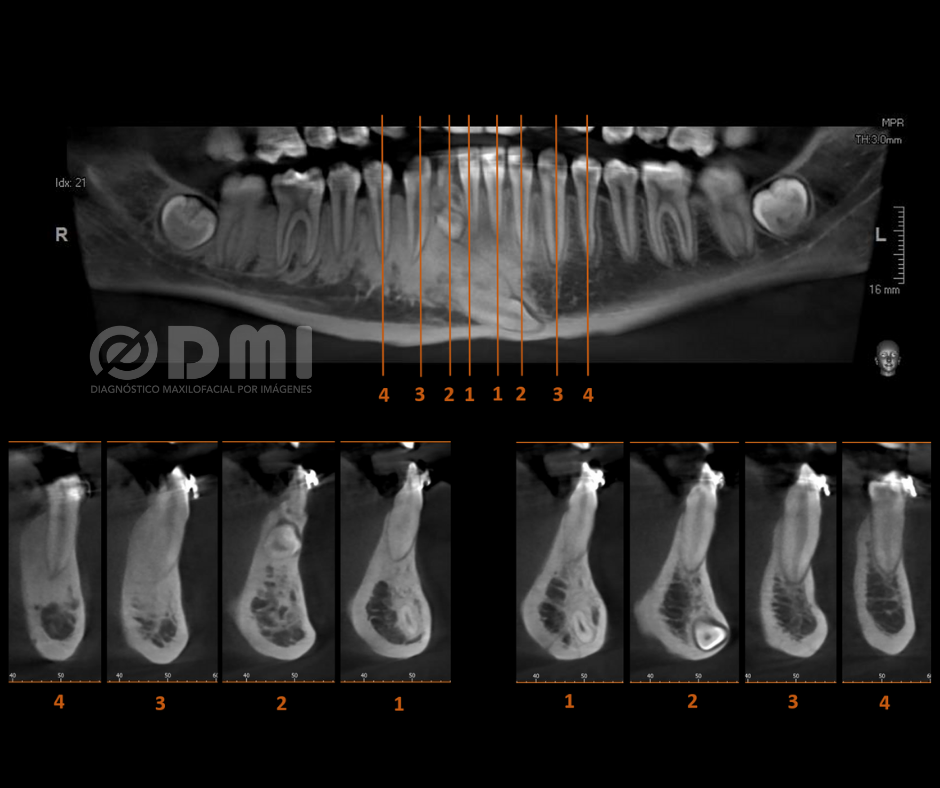

Mediante el corte transaxial podemos corroborar la presencia de una lesión osteolítica expansiva de forma esférica, límites definidos y bordes corticalizados, ubicada en la región para radicular del lado izquierdo entre las raíces de los Od No. 33 y 34 que ocasiona expansión de corticales, sugerente de Quiste Radicular. Se recomienda análisis histopatológico.